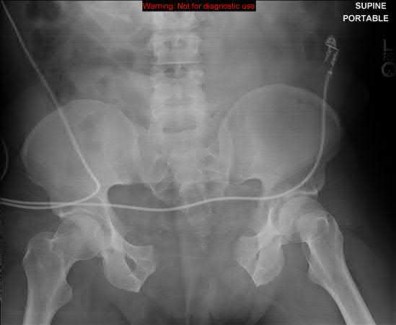

A 23-year-old female is an unrestrained driver in a motor vehicle collision, sustaining the injury shown in Figure A. She subsequently undergoes reduction and percutaneous bilateral iliosacral screw placement. Which of the following is the most likely neurologic complication associated with percutaneous iliosacral screw insertion?

Figure A shows an unstable bilateral pelvic ring injury. Percutaneous posterior iliosacral screw fixation places the L5 nerve root at risk as it courses across the sacral ala. Injury to the L5 nerve root would typically result in weakness in great toe extension and sensory changes on the dorsum of the foot. It is important to notice that L5 often partially innervates tibialis anterior along with L4, so weakness to ankle dorsiflexion may be present as well. Illustration A shows the post-operative films with bilateral iliosacral screws.

Routt et al examined the sacral slope and sacral alar anatomy in cadavers and a series of consecutive patients. They determined that the pelvic outlet and lateral sacral plain films provide the best plain radiographic views of the sacral ala. They recommended routine usage of these views intraoperatively to guide screw placement.

In another study, Routt et al reported on the early complications of percutaneous placement of iliosacral screws for treatment of posterior pelvic ring disruptions. While technically challenging, this technique leads to less blood loss and lower rates of infection compared to traditional open techniques.

Illustration B displays the root diagrams for sensation, reflex, and motor of the L4-S1 nerves.